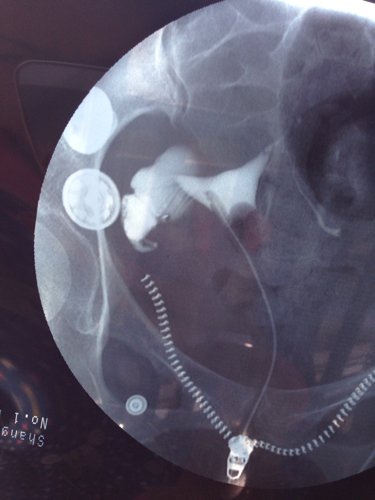

两年前我做过宫外孕腹腔镜手术,前几天去做了输卵管造影,做腹腔镜那侧不通另侧积水!我应该怎样治疗! 点击展开 匿名用户 2014-03-22 23:33 为您推荐: 其他回答 病情分析: 您的情况应该是输卵管炎症的表现。 指导意见: 可考虑通水治疗。把舌头的照片发一张过来看看。可考虑请中医大夫看看,选用中药如桂枝茯苓丸、当归芍药散、妇炎康来调治。 虞静涵_slGJ 2014-03-23 05:02 相关问题 我去年得过一次宫外孕做过一次腹腔镜手术 现在输卵管堵塞还有积水 医生又建议做腹腔镜手术 会影响吗 宫外孕腹腔镜手术后是否需要做输卵管造影? 宫外孕腹腔镜手术时医生说另一侧输卵管是通的,我还需要做造影检查吗